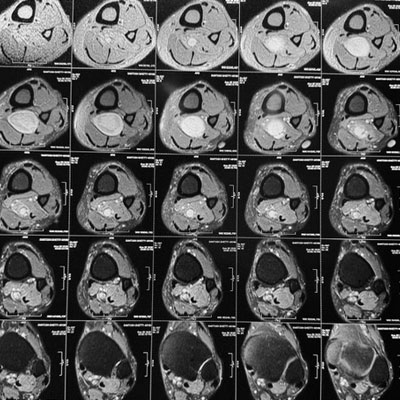

Surgical Highlights